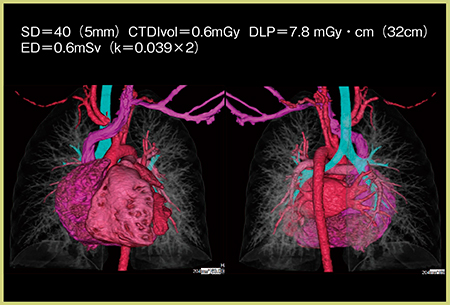

当院の小児循環器撮影プロトコールは,回転速度275ms,管電圧80kV,SD40(5mm:AIDR 3D Enhanced使用時はSD32),ECG同期volume撮像,Target CTA@40%,1心拍となっている。症例4は,3歳,女児,体重10.2kg,Ebstein症候群の症例だが,QDS,AIDR 3D Enhanced Strongではノイズは抑えられているものの,全体的に輪郭が不鮮明になっている(図5)。FIRSTのCardiac Strong(図5 c)では,心臓の輪郭を追うことができ,右房と右室の間の形状や,巨大化した右室に圧排された肺静脈の狭窄なども確認できる。図5 cのFIRSTのデータから作成した3D画像(図6)は,肺血管を含めて心臓全体が高い精度で描出されており,FIRSTの高い空間分解能が確認できる。CTDIvolは0.3mGy,EDは0.6mSvである。

図6 図5 cのFIRST(Cardiac Strong)のデータから作成した3D再構成画像